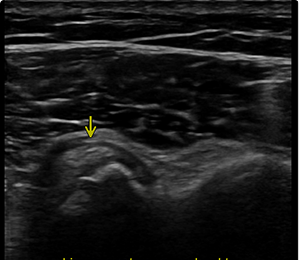

Orthopedische echografie, een blessure nader bekeken .........

Wij beschikken over mobiele echo-apparatuur met haarscherp beeld!